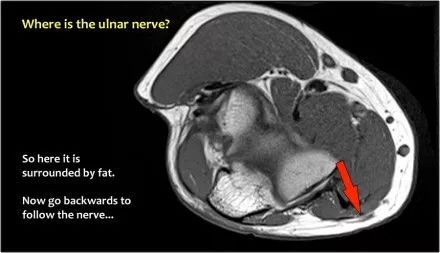

尺神经:在这里,我们看到了肘管内的尺神经。尺骨侧支带的后带形成隧道的底部,而支持带形成屋顶。

因此,当我们回到图像时,您会发现很难找到神经。任何这些皮下结构都可以是转位神经。一种方法是远端跟随结构,直到你发现远端的尺神经位于由脂肪包围的前臂近端的正常位置。然后当你向近端跟随它时,你会发现这是皮下移位。

在这种情况下,有神经炎。神经增大。在T2W图像上有高信号。另一个标志是在矢状图像(箭头)上看到的束的不均匀扩大。